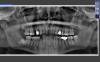

tonko Опубликовано 13 января, 2011 Поделиться Опубликовано 13 января, 2011 Посоветуйте что лучше сюда (обл 15 и 44) поставить . Есть два варианта - мис или кортекс. Нужен совет какой именно имплант, какой длины и диаметра. Толщины альвеоляра хватает, биотип толстый. Заранее спасибо. Ссылка на комментарий

Bier Опубликовано 14 января, 2011 Поделиться Опубликовано 14 января, 2011 ставьте тонкий у МИСа 3,75 а длины 11,5 достаточно. Ссылка на комментарий